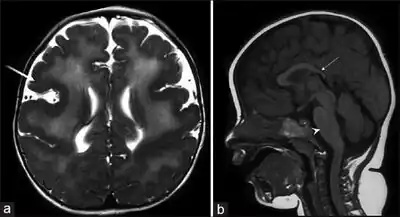

a,b) MRI[6] of brain stem malformation

Magnetic resonance imaging of the brain shows abnormalities of the corpus callosum and cortical dysplasia, with pachygyria and polymicrogyria.